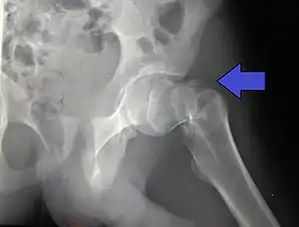

X-rays of the affected hip usually make the diagnosis obvious; AP (anteroposterior) and lateral views should be obtained.

Intracapsular fractures

For low-grade fractures (Garden types 1 and 2), standard treatment is fixation of the fracture in situ with screws or a sliding screw/plate device. This treatment can also be offered for displaced fractures after the fracture has been reduced.

In elderly patients with displaced or intracapsular fractures surgeons may decide to perform a hemiarthroplasty, replacing the broken part of the bone with a metal implant.[36] However, in elderly people who are medically well and still active, a total hip replacement may be indicated. Independently mobile older adults with hip fractures may benefit from a total hip replacement instead of hemiarthroplasty.[37]